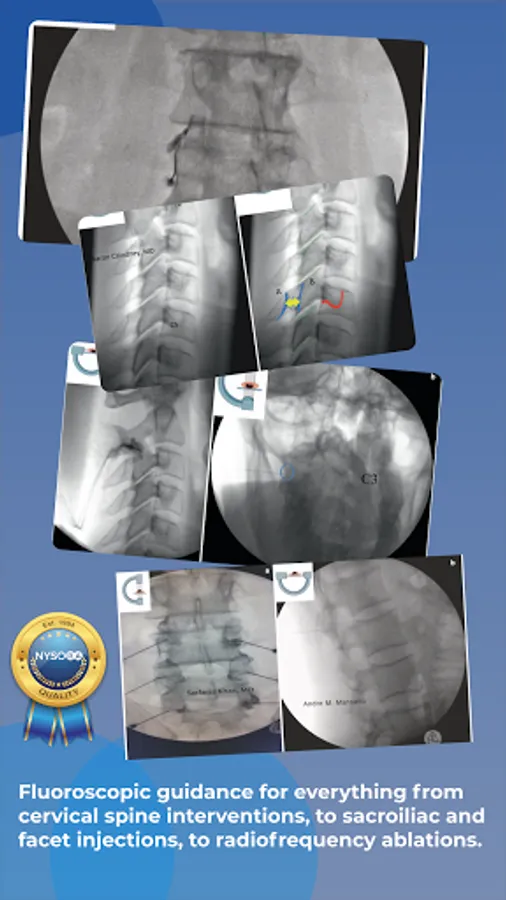

Standardized Fluoroscopy-Guided Interventional Pain Procedures

Interventional Pain App details in step-wise fluoroscopic approach evidence-based interventional pain procedures with the focus on Standards, Safety & Efficacy..

Images, illustrations, functional anatomy, and recommended interventional pain blocks and procedures.

Fluoroscopy-guided interventions: Interlaminar Cervical Epidural Injection, Intra Articular Cervical Facet Joint Block, C2-T1 – Posterior and Lateral Approach, Intercostal Nerve Block, Sacroiliac Joint Injection, Sacroiliac Joint Radiofrequency Ablation (Bipolar Palisade Technique), Superior Hypogastric Plexus Block – Anterior Approach, Neuroplasty (Caudal, Transgrade and Transforaminal approach), Superior Hypogastric Plexus Block – Transdiscal Approach, Splanchnic Block and Radiofrequency Ablation